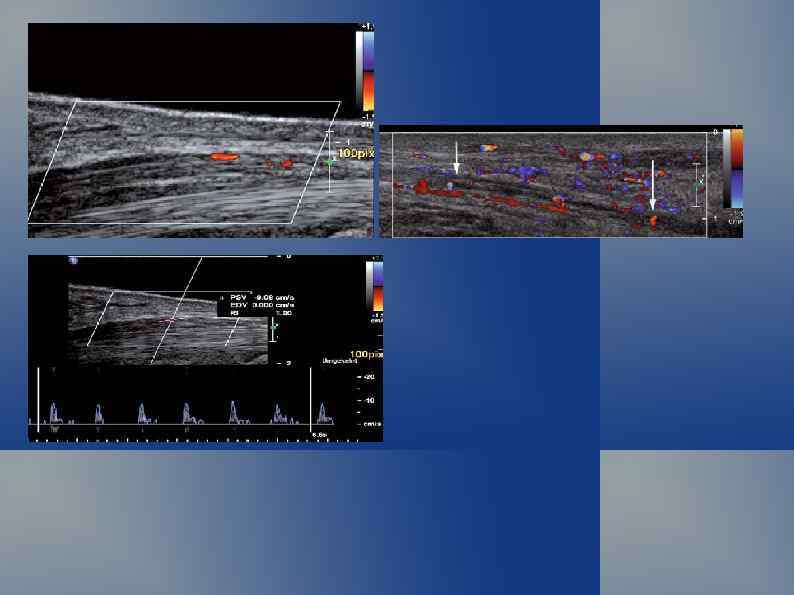

Режимы ЦДК и ЭД позволяют изучить васкуляризацию

Турбулентный высокоскоростной поток в зоне ангиоматоза.